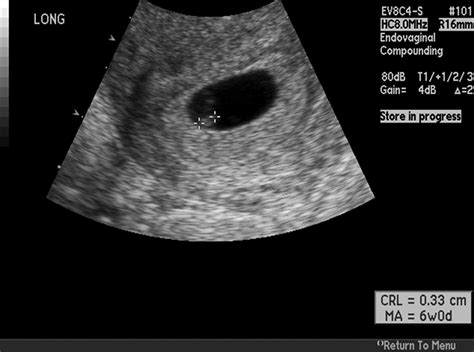

• Gestational Sac: The presence of a gestational sac confirms the pregnancy. It appears as a small, fluid-filled structure within the uterus.

• Yolk Sac: By week 6, a yolk sac may be visible. This structure provides early nutrition to the embryo and is a positive sign of a healthy pregnancy.

• Fetal Pole: The fetal pole is the earliest visible structure of the embryo. It appears as a small, curved line within the gestational sac.

• Fetal Heartbeat: A fetal heartbeat may be detectable by week 6, although it is more commonly seen by week 7. The heartbeat appears as a flickering motion on the ultrasound screen.